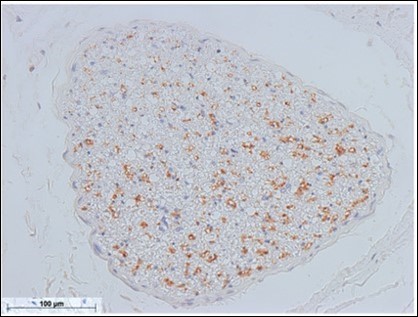

Based on the results obtained in this study, the mental nerve and the marginal mandibular branch of the facial nerve are completely fused at the perineurium. Most nerve diagrams indicate that the mental nerve is only a sensory nerve, and that the marginal mandibular branch of the facial nerve is a pure motor nerve. However, we found that there is a need for autonomic nerves to be present in the lower face region, where there are salivary glands and sweat glands, including the lower lip and chin (the regions of these nerves). Hence, we aimed to determine where these nerves originate. In the present study, we observed that the vasomotor nerve of the facial artery branched off from the buccal branch and the marginal mandibular branch of the facial nerve (Figure 2※), and we identified the fact that there are sympathetic and parasympathetic fibers in the facial nerve. This was also confirmed micro-anatomically. Figure 5 shows a cross-section of the optic nerve, and Figure 6 shows a cross-section of the mental foramen region of the mandibular nerve. Tyrosine hydroxylase immunostaining stained the sympathetic nerves (provided by lecturer Masahito Yamamoto of the Department of Anatomy, Tokyo Dental College). The trigeminal nerve includes sympathetic fibers, and when the two sections are compared, the optic nerve has a substantial number of such fibers, whereas the mandibular nerve has very few. Matsubayashi 10 wrote extensively on this issue. It is known that the trigeminal nerve, which is the great auricular nerve, auriculotemporal nerve, and zygomatic branch of the facial nerve, consists of cutaneous nerves of the face and sympathetic nerve fibers, although there are few sympathetic nerve fibers in the maxillary nerve or mandibular nerve.

Figure 5.Sympathetic nerve fibers of the optic nerve (anterior facial nerve: TH staining) Bar = 100um